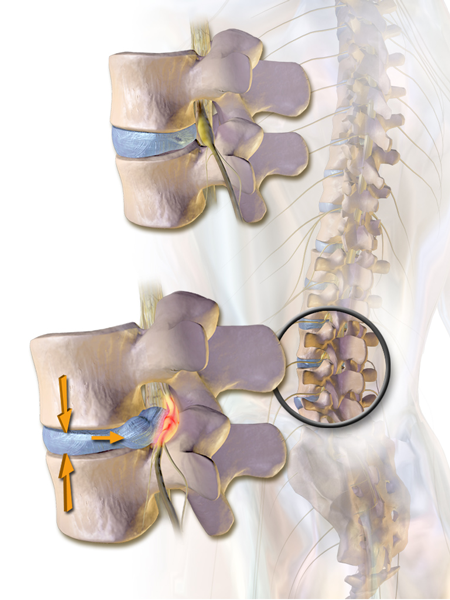

Κήλη οσφυϊκού μεσοσπονδυλίου δίσκου (κάτω), με στένωση του νευρικού τρήματος και πίεση του εξερχόμενου νεύρου. Σύγκριση με φυσιολογικό δίσκο, τρήμα στην άνω εικόνα. |